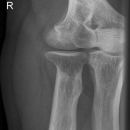

Ellenbogen ventro-dorsal (1. Ebene a.-p.)

Beurteilungskriterien

- Lage der Tuberositas radii zeigt die Stellung des Unterarms: Supination -> Tuberositas zeigt nach medial, Pronation -> Tuberositas zeigt nach lateral

- Physiologische Valgusstellung von 10 – 15°

- Ellenbogengelenkspaltweite: etwa 3mm

- Auftreten, Verschmelzung und Lokalisation der Epiphysenkerne -> Verlagerung? vgl. Anatomie Kids! Viele kindliche Verletzungen sind anhand der Verlagerung der Knochenkerne differenzierbar! Evtl. Vergleich mit Gegenseite oder MRT hilfreich.

- Target areas: Kontinuität der Knochenkontur der Fossa olecrani , der Epikondylen und Kondylen, des Olecranons.

Harmonische Darstellung des Radiusköpfchens? Impressionen? Stufe? Verdichtungen, Fissur? Knickbildung im leicht geschwungenen Radiuskopf-/Hals-Übergangs?

Cave: 50% der Radiusköpfchenfraktur sind nicht disloziert und u.U. nicht nachweisbar -> bei klinischem Verdacht ist ein positives Fettpolsterzeichen in der seitlichen Aufnahme nahezu beweisend! -> Greenspan-Aufnahme, evtl. CT oder MRT!

- Erhaltene Radius-Kapitulum-Achse? Versatz -> Luxation?

- Täuschungsmöglichkeiten: Persistierende Apophysen an Epikondylus medialis, Olecranonspitze, medialem Trochlearand oder Processus coronoideus

- Umgebende Leitungsbahnen: besonders gefährdet bei stark dislozierten Verletzungen sind der N.ulnaris (verläuft im seiner Knochenrinne durch den distalen mediodorsalen Humerus und die A.brachialis (zusammen mit N.medianus ventral des Gelenks)

- Kids: Baumannscher Winkel: Humeruslängsachse – Gerade durch die Epiphysenfuge des Capitulums ~ 70-75°. Wichtig für die Beurteilung der Repositionskontrolle nach supracondylärer Humerusfraktur